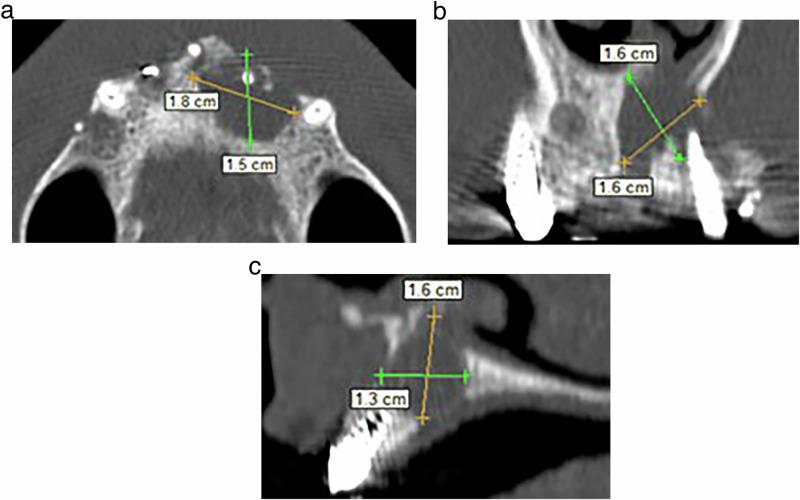

A randomized controlled trial was conducted on 41 patients who had 60 permanent teeth in the maxillary incisors that were accompanied by large-sized periapical lesions. The included teeth were radiographed with cone beam computed tomography (CBCT) images and divided equally into two groups according to the endodontic treatment statute (30 untreated previous cases and 30 retreated cases). Subsequently, teeth received uniform preparation, irrigation, and dressing procedures. Then each group was divided equally according to the used sealer (15 teeth obturated using AH plus sealer with LCT and 15 teeth obturated using BC sealer with SCT). All cases were followed up after 6 and 12 months with CBCT images. Subsequently, the change in periapical lesion diameter (PLD) was observed as an indicator to determine the treatment outcome score. One-way ANOVA and Mann-Whitney U test were used to analyze the PLD changing and scoring the treatment outcome during the follow-up periods. The significance level was set at α = 0.05.

对41例上颌切牙有60颗恒牙且伴有大型根尖周病变的患者进行了一项随机对照试验。纳入的牙齿用锥形束计算机断层扫描(CBCT)成像进行放射照相,并根据牙髓治疗情况平均分为两组(30例既往未治疗病例和30例再治疗病例)。随后,对牙齿进行统一的预备、冲洗和换药程序。然后根据所用封闭剂将每组再平均分为两组(15颗牙齿使用AH plus封闭剂和LCT进行根管充填,15颗牙齿使用BC封闭剂和SCT进行根管充填)。所有病例在6个月和12个月后用CBCT图像进行随访。随后,观察根尖周病变直径(PLD)的变化作为确定治疗结果评分的指标。采用单因素方差分析和曼-惠特尼U检验分析随访期间PLD的变化及治疗结果评分。显著性水平设定为α = 0.05。